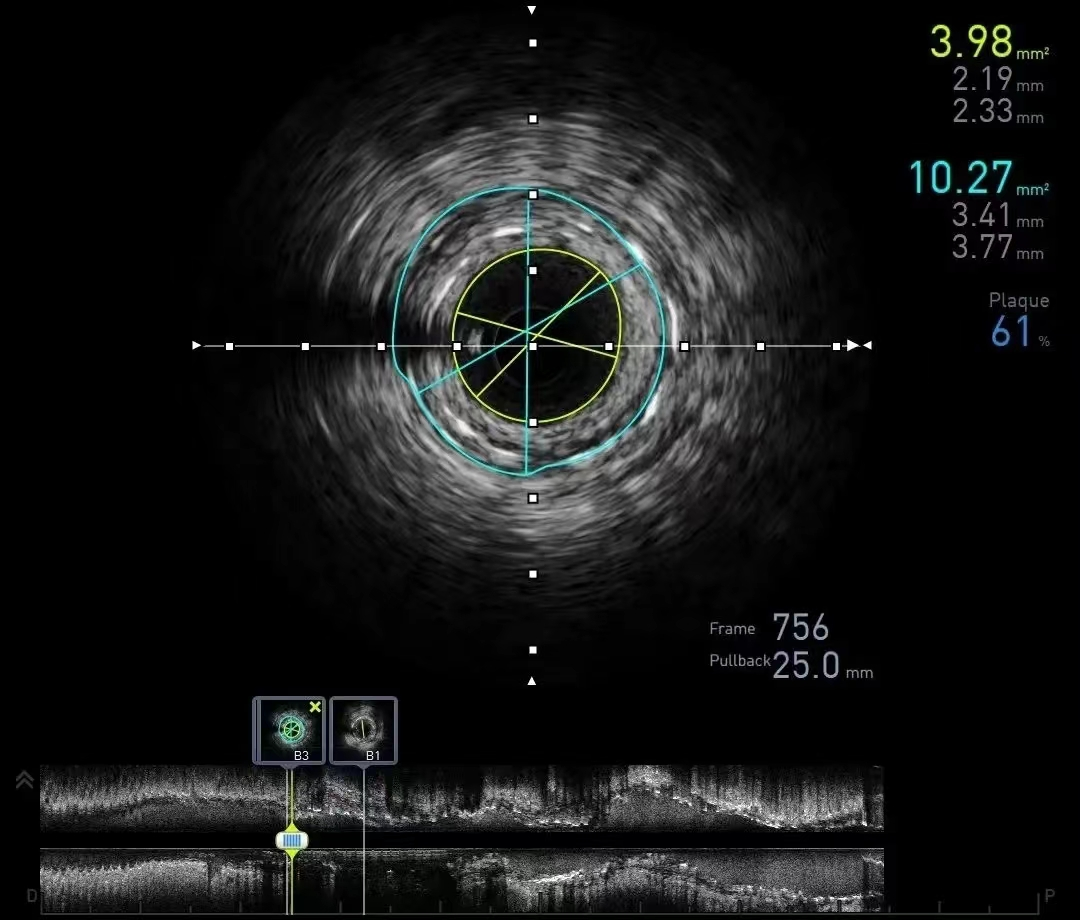

3、超声和血管内超声 4、冠脉CT

5、冠状动脉造影:是目前冠心病诊断的“金标准”